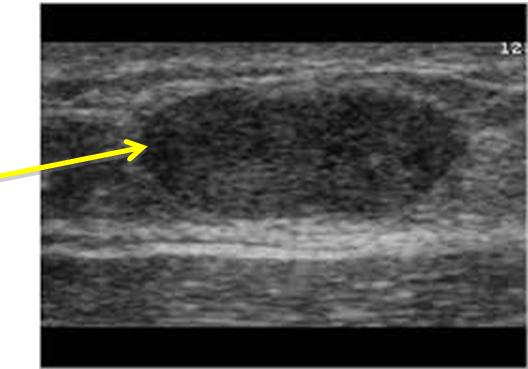

Siêu âm tuyến vú: Vị trí 4h cách núm vú phải 3cm có khối giảm âm đồng nhất, bờ đều. Phần nhu mô còn lại không thấy nốt hay khối bất thường.

Hình ảnh nốt kích thước: 1,6x1,2cm vị trí 1/4 dưới trong vú phải

tăng hấp thu FDG, max SUV=2,8.